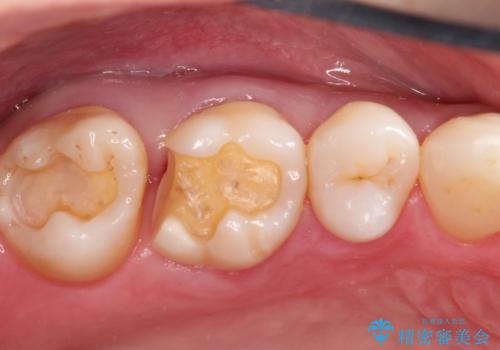

むし歯の治療。ゴールドインレーによる修復

- 定期健診にてむし歯を認めたためゴールドインレーにて治療を行いました。

拡大鏡で常に口腔内を診察しているため、小さなむし歯も見逃さずに治療を行っています。